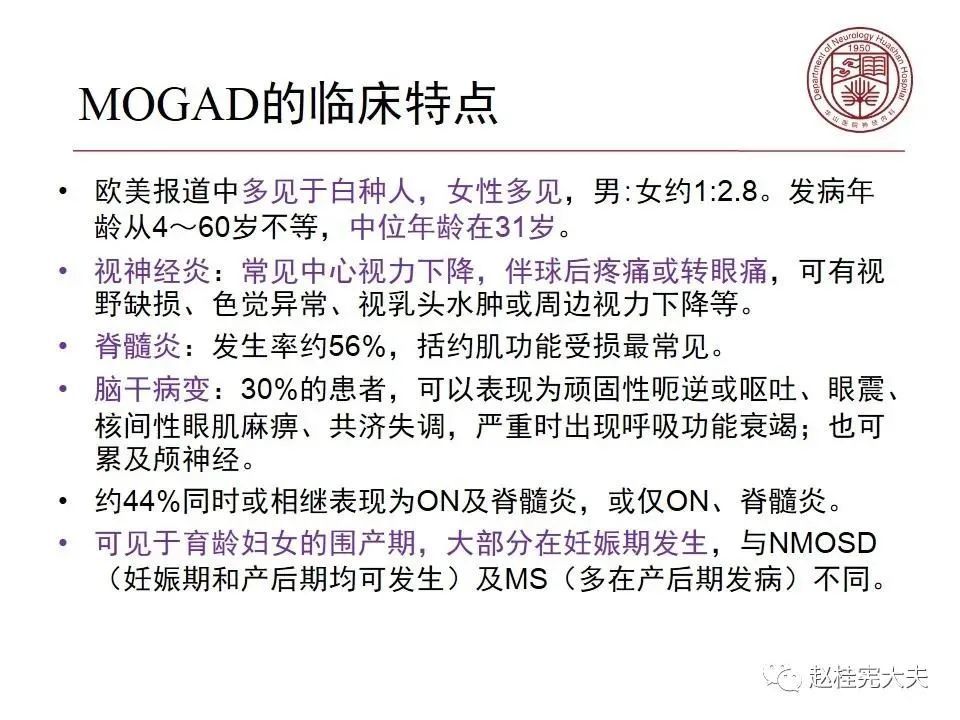

就是一种由MOG抗体介导的中枢神经系统自身免疫性疾病,目前被命名为MOG抗体相关性疾病,即MOGAD,在AQP4抗体未被发现,NMO/NMOSD还没有从MS分离出来时被诊断为MS,当NMO/NMOSD因AQP4抗体的发现从MS分离出后,它被诊断为NMO/NMOSD,在前几年,在一些AQP4抗体阴性的NMOSD患者中发现了MOG抗体阳性,MOG抗体相关性疾病才被认识,曾被命名为MOG脑脊髓炎,终于在2年前正式被命名为MOG抗体相关性疾病,当然,目前还有不少同道还将MOGAD诊断为NMOSD,按照其发病机制和分子靶部位,MOGAD和NMOSD是不同的,应该将其单独列为一个疾病去诊治。(个人意见,欢迎指正和讨论!)